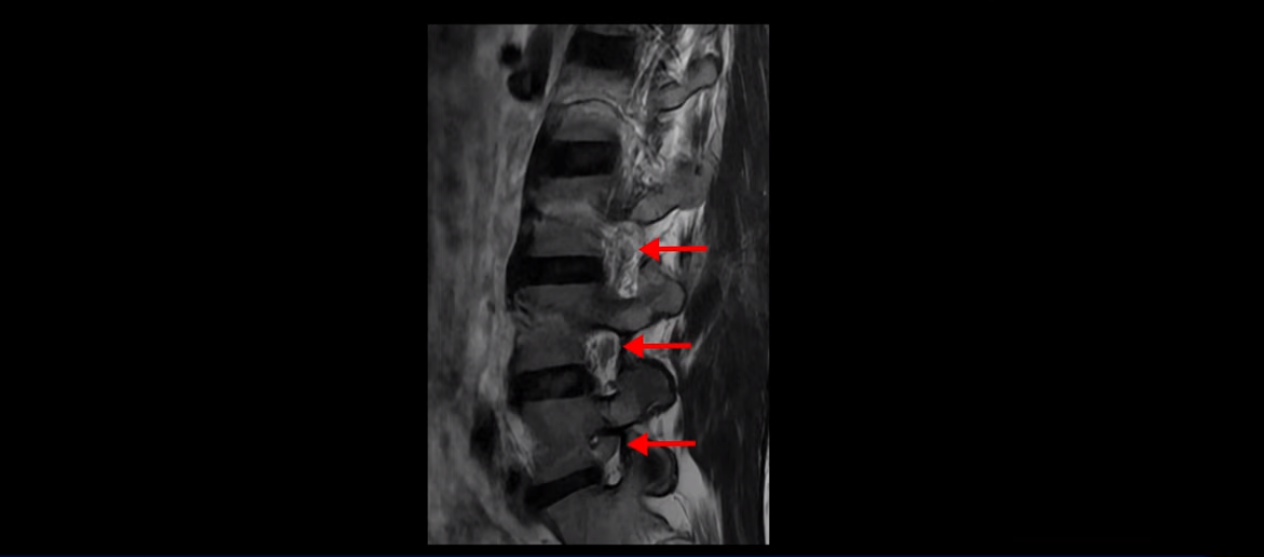

우선 이분 허리 MRI를 보면 5번 1번에 퇴행성 디스크가 있지만 방사통을 일으킬 만큼 신경을 누르고 있어 보이지 않습니다.

오른쪽으로 디스크가 약간 찢어져 보이는데, 작년에 찍은 MRI에서도 보이는 것이라 오래 전에 찢어진 후 아문 흔적으로 보입니다.

중요한 것은 오른쪽 다리에 심한 방사통이 있다든가 재채기를 못 한다거나 허리를 구부리거나 몸을 살짝 비틀 때 날카로운 통증이 없습니다. 즉, 섬유륜이 최근에 찢어진 게 아닌 겁니다.

4번 5번과 3번 4번 마디도 디스크가 중앙으로 살짝 밀려나와있지만 최근에 섬유륜이 찢어진 것도 아니고, 신경 다발을 누를 정도로 심하게 밀려나와 있는 것도 전혀 아닙니다.

양쪽 신경 가지가 빠져나가는 추간공도 충분히 넓어서 신경학적 방사통을 일으킬 여지가 없습니다.